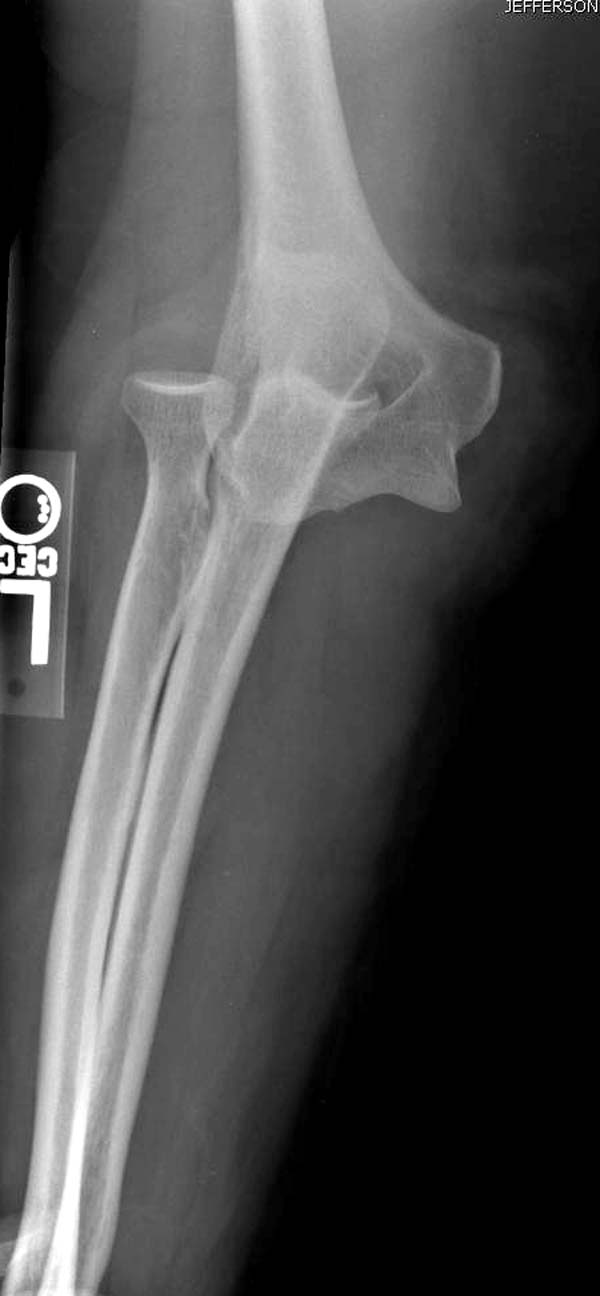

В данном случае имеется, так называемая, "ужасная триада" локтевого сустава, включающая перелом головки лучевой кости, перелом венечного отростка и вывих костей предплечья кзади, также в структуру травмы входит повреждение латерального коллатерального связочного комплекса и возможно передней порции медиальной коллатеральной связки. Лечение состоит из следующих этапов: фиксация венечного отростка( анкер или проволочная петля типа лассо), далее остеосинтез или протезирование головки лучевой кости ( КТ было бы желательно, фотографии не особо четкие), затем шов латерального коллатерального связочного комплекса. Если сохранится нестабильность, потребуется или шов передней порции медиальной коллатеральной связки с иммобилизацией верхней конечности аппаратом внешней фиксации (желательно с сохранением движений в локтевом суставе) или только аппарат(мнения расходятся). Аппарат 6 недель. Результаты лечения таких повреждений не очень хорошие.

Для примера здесь случай начатый в другом центре, а потом переправленный к нам.

Снимки: 1-2 вывих, 4-5 вторичное смещение в гипсе, реконструкция латеральной связки и капсулы 13-14, повторный вывих после реконструкции, перевод в наш центр; 18-21 временная фиксация, 22-25 трансартикулярная фиксация и нестабильная головка фиксирована спицами, 29-30 амбулаторно, 32-33 после удаления винта и спиц...